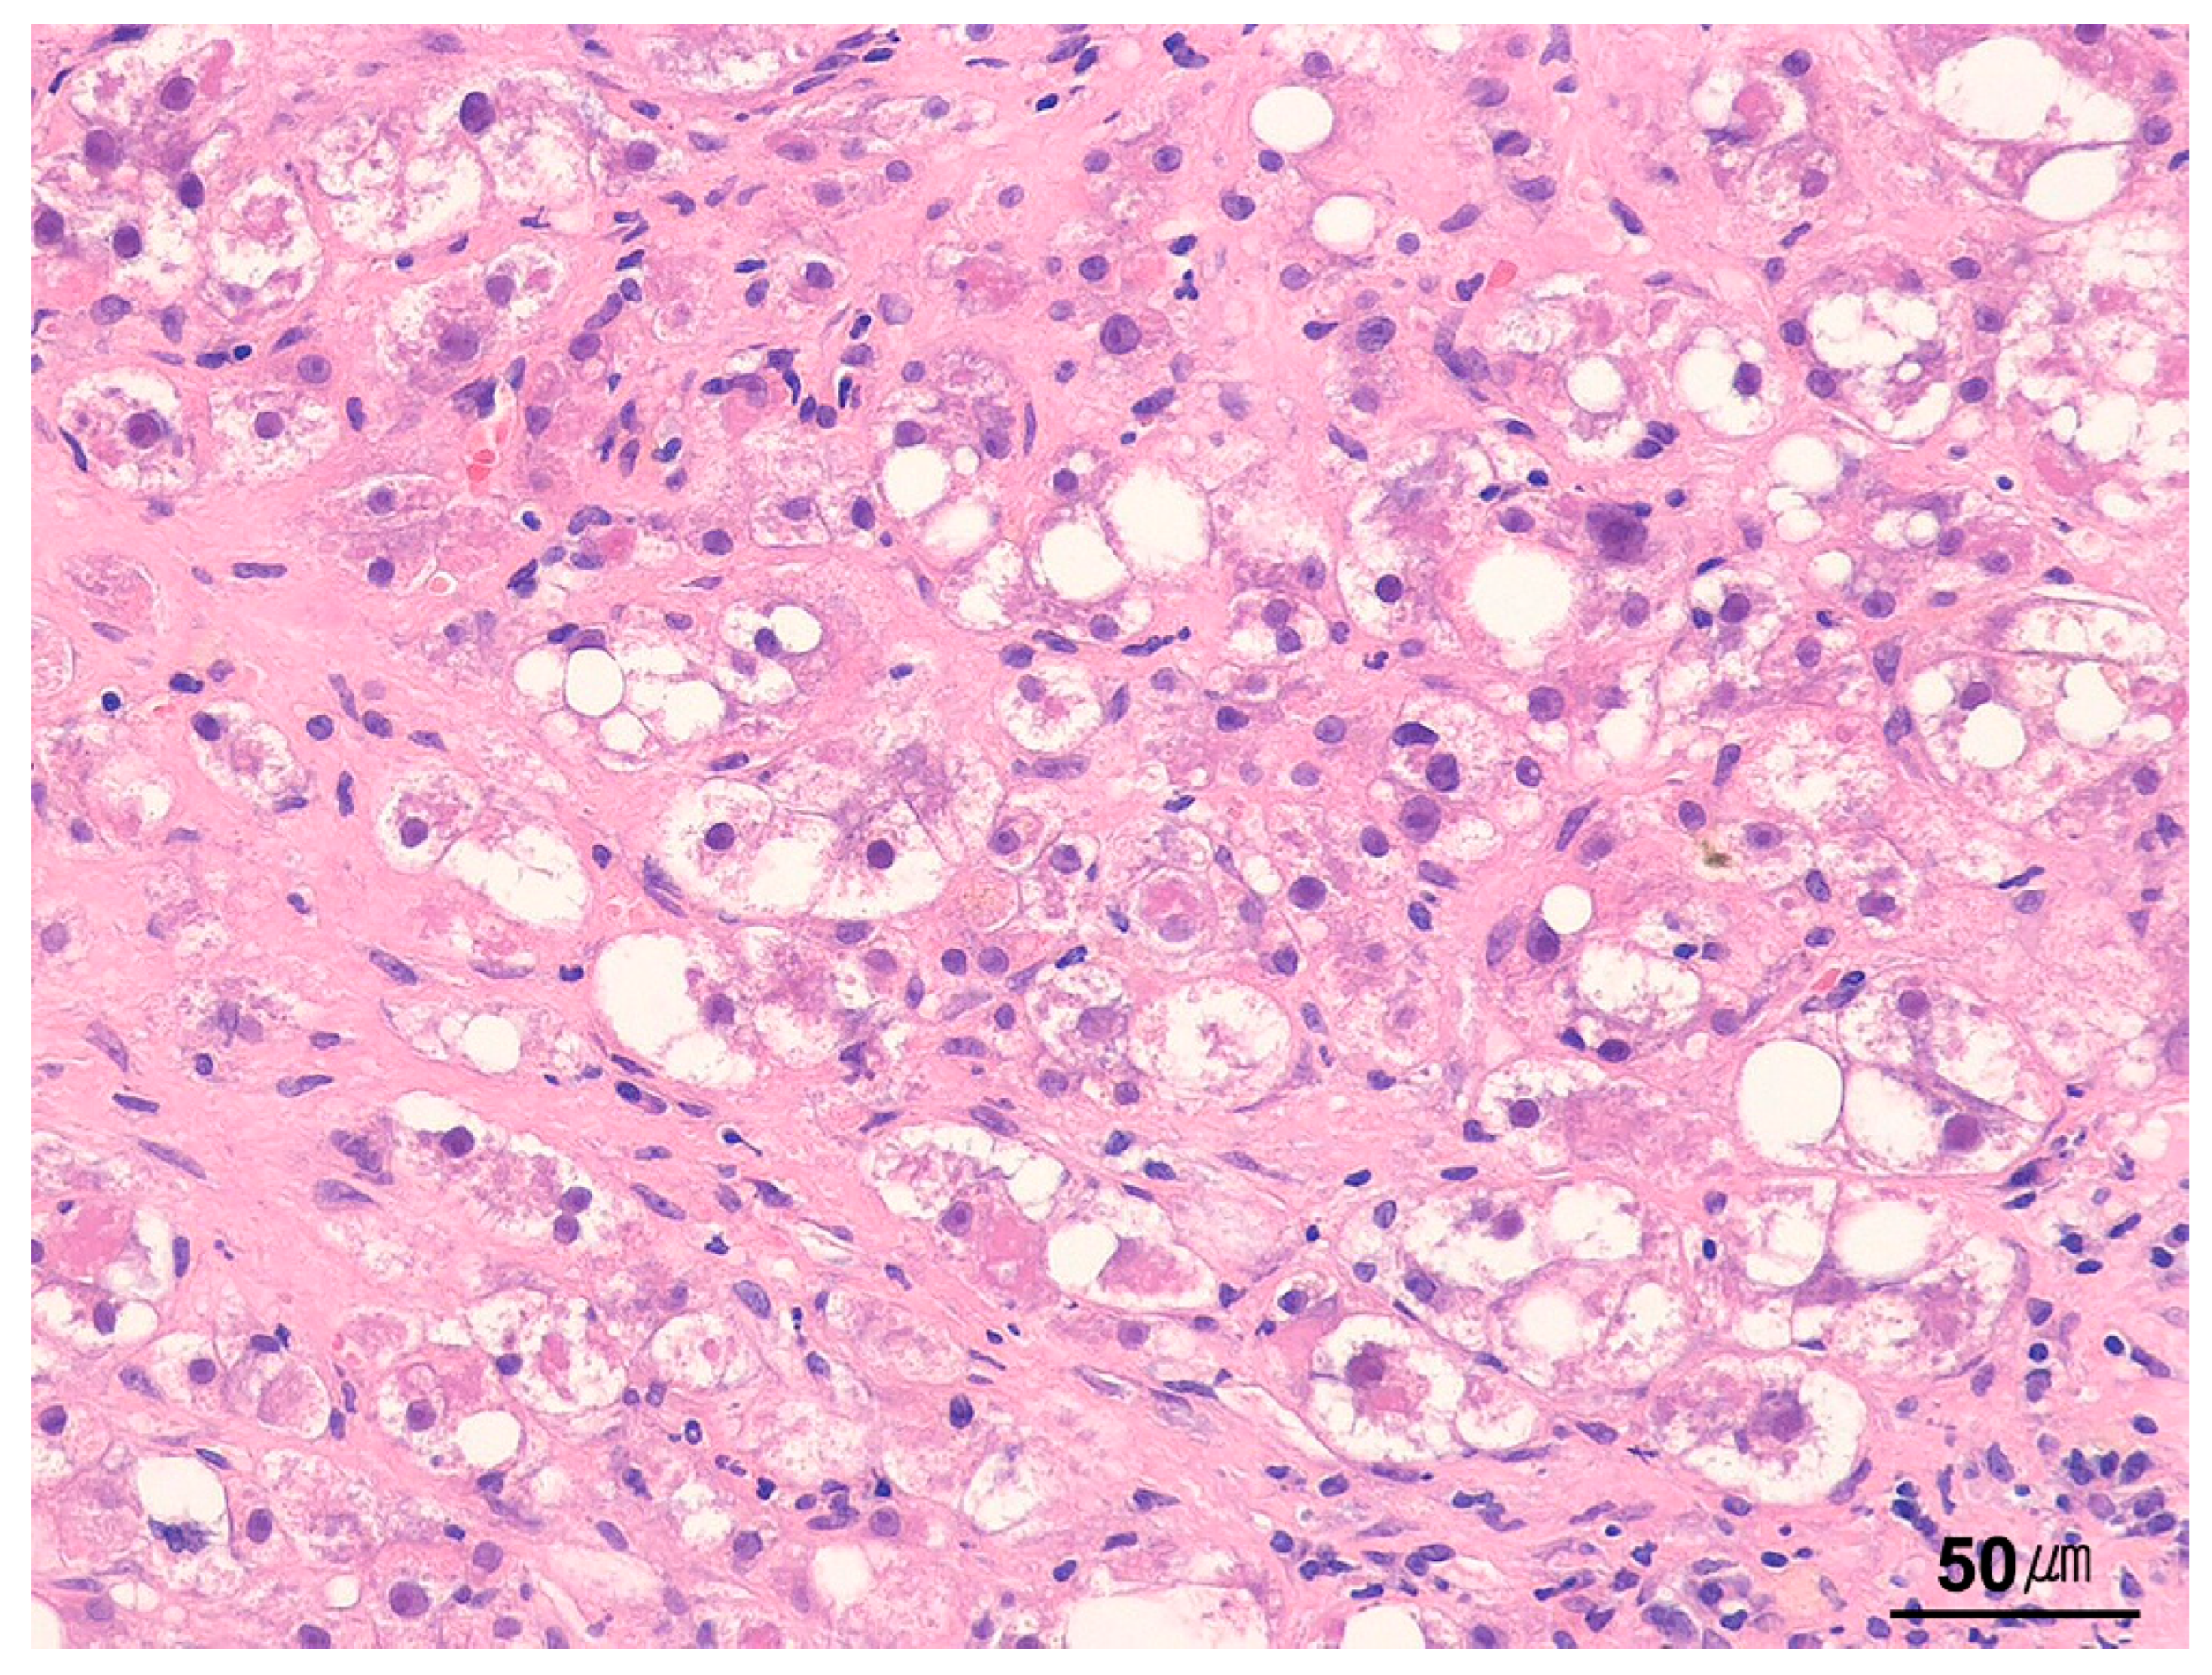

9.4. Cytoplasmic Changes and Inclusions in Hepatocytes

9.4.2. Ballooned Hepatocytes

| Steatotic pattern | Macrovesicular steatosis Microvesicular steatosis | Alcohol-associated liver disease NAFLD/NASH (metabolic syndrome) DILI |